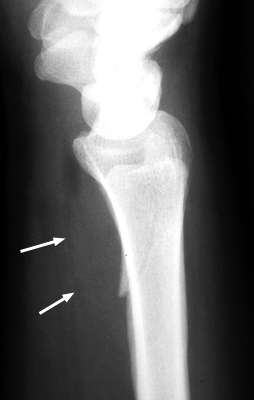

Diagnosis:Wrist Fracture Discussion:A. Normal pronator fat pad. B. Displaced pronator fat pad. Lateral wrist x-ray, a reveals abnormal bulging of a fat plane adjacent to an area of underlying osseous injury. The ventral bulging of the fat plane overlying the pronator quadratus muscle has been coined the "pronator sign." Although it typically means underlying fracture is present, it may also be seen in simple soft-tissue injury of the same region. It is a good sign and should alert the radiologist of possible fracture when present. References: